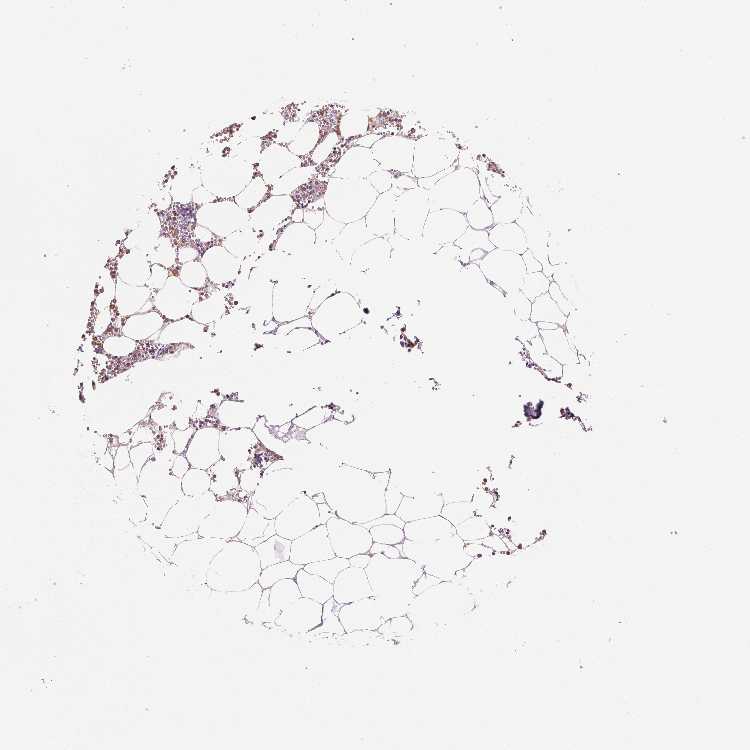

BONE MARROW - Antibody stainingi

Antibody staining in the annotated cell types in the current human tissue is reported as not detected, low, medium, or high, based on conventional immunohistochemistry profiling in selected tissues. This score is based on the combination of the staining intensity and fraction of stained cells.

Each image is clickable and will lead to virtual microscopy that enables deeper exploration of all samples and also displays staining intensity scores, fraction scores and subcellular localization as well as patient and tissue information for each sample.

Antibody HPA021147Antibody HPA061464Antibody CAB000059Antibody CAB080352Antibody CAB080353Antibody CAB080354

Hematopoietic cells LowHighMediumHighHighHigh